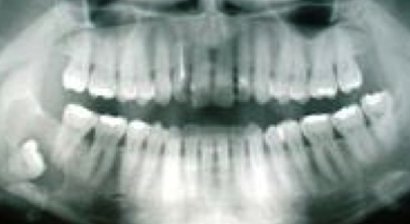

Der Weisheitszahn Der Weisheitszahn ist von der Mitte aus gezählt der achte Zahn im menschlichen Gebiss. Normalerweise hat ein Mensch vier Weisheitszähne, in jedem Gebissquadranten einen. Sie brechen meist erst im Erwachsenenalter, teilweise gar nicht durch. Die Anzahl der Wurzeln ist unte...